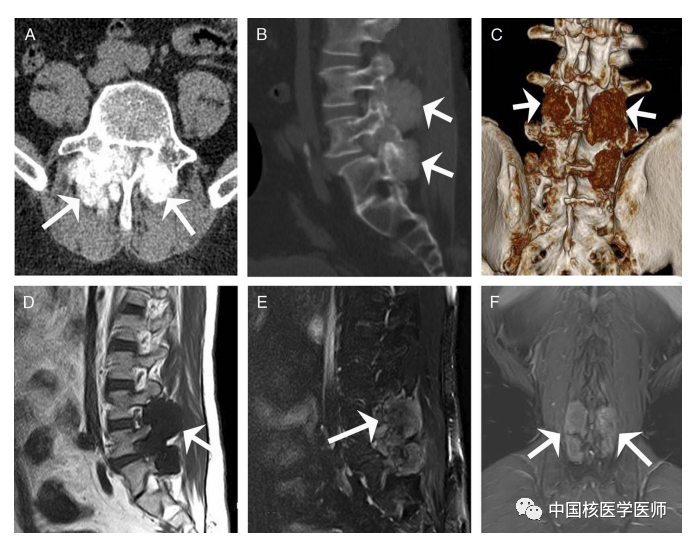

圖1. 一名53歲男性,既往患有10年痛風性關節炎和痛風石病史,累及雙膝、雙手、肘部和肩部。最近,他因“進行性腰痛”來我院就診。血尿酸水平為645 μmol/L(參考值范圍240 ~ 490 μmol/L)。腰部CT及三維圖像重建顯示L3至L5節段高密度腫塊,橫斷面圖像顯示雙側椎小關節周圍骨質破壞(圖A,箭頭)、矢狀面(圖B,箭頭)和三維圖像(圖C,箭頭)。首先懷疑為成骨轉移瘤,其次懷疑為腰椎骨軟骨瘤。為了評估病變的程度和脊髓受累情況,患者隨后進行了MRI檢查,結果顯示與周圍肌肉相比較,腫塊在T1加權圖像(D,箭頭)上呈低信號,T2加權圖像上呈稍高信號(E和F,箭頭)。此外,MRI顯示前側硬膜囊輕微受壓,此種表現提示其可能為惡性腫瘤,并伴有硬膜囊及脊髓壓迫。